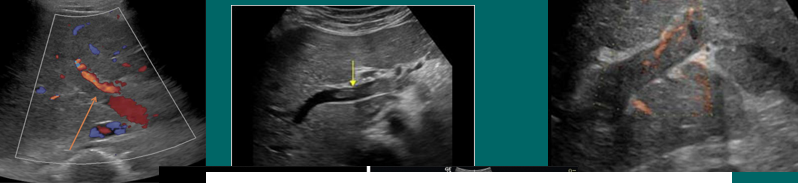

HA thrombosis

HAT

hepatic artery stenosis (HAS)

HA to PV fistula (AVF)